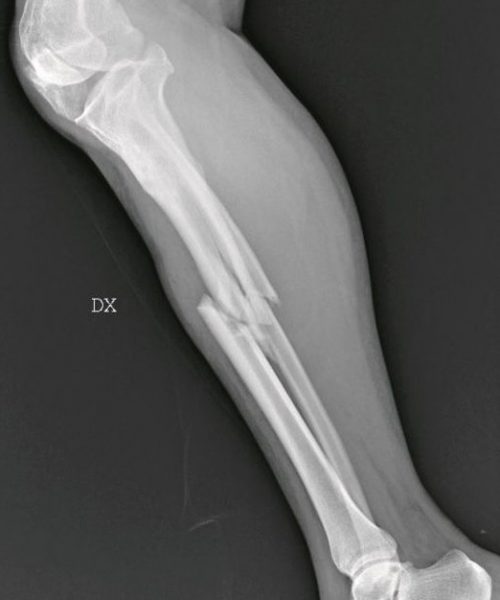

Με την ευκαιρία αυτή, στο μιλανέζικο νοσοκομείο Σαν Κάρλο και με πρωτοβουλία της ιατρού Μαρία Γκράτσια Βανταντόρι, 59 ετών, χειρουργού επί 26 χρόνια εκεί, γίνεται έκθεση ακτινογραφιών γυναικών οι οποίες προσήλθαν στο νοσοκομείο κατόπιν σοβαρού τραυματισμού τους. Οι ακτινογραφίες, λέει η ιατρός στη ρεπόρτερ της La Repubblica, δείχνουν την οικογενειακή βία που υφίστανται οι γυναίκες.

«Εδώ είναι η καθημερινή φρίκη που αντικρίζουμε στα έκτακτα περιστατικά. Συχνά οι τραυματισμένες γυναίκες δεν έχουν τη δύναμη να πουν τι τους έχει συμβεί, αλλά τα σώματά τους και τα τραύματά τους μιλούν από μόνα τους». Η ιατρός περιγράφει τα συνήθη: «Σπασμένα οστά σε μύτη, χέρια, πόδια, πληγές από μαχαιριές, εγκαύματα, μελανιές και άλλα σημάδια στραγγαλισμού». Αλλά και τα ασυνήθη: «Μέχρι και με ένα μαχαίρι καρφωμένο στην πλάτη της μας ήρθε μια γυναίκα».

Ετσι η Βανταντόρι αποφάσισε να εκθέσει «εικόνες από έναν αόρατο πόλεμο που διεξάγεται καθημερινώς πίσω από τους τοίχους των σπιτιών», δηλαδή τις ανώνυμες ακτινογραφίες οι οποίες δείχνουν τα βασανιστήρια που υπέστησαν οι γυναίκες «από συζύγους, πρώην συζύγους, συντρόφους». Η ρεπόρτερ του ιταλικού φύλλου χαρακτηρίζει την έκθεση «ακραία και τραγική».